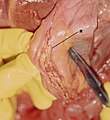

Gross

- Entry intimal tear +/- exit intimal tear.

- Blood between layers of the vessel wall.